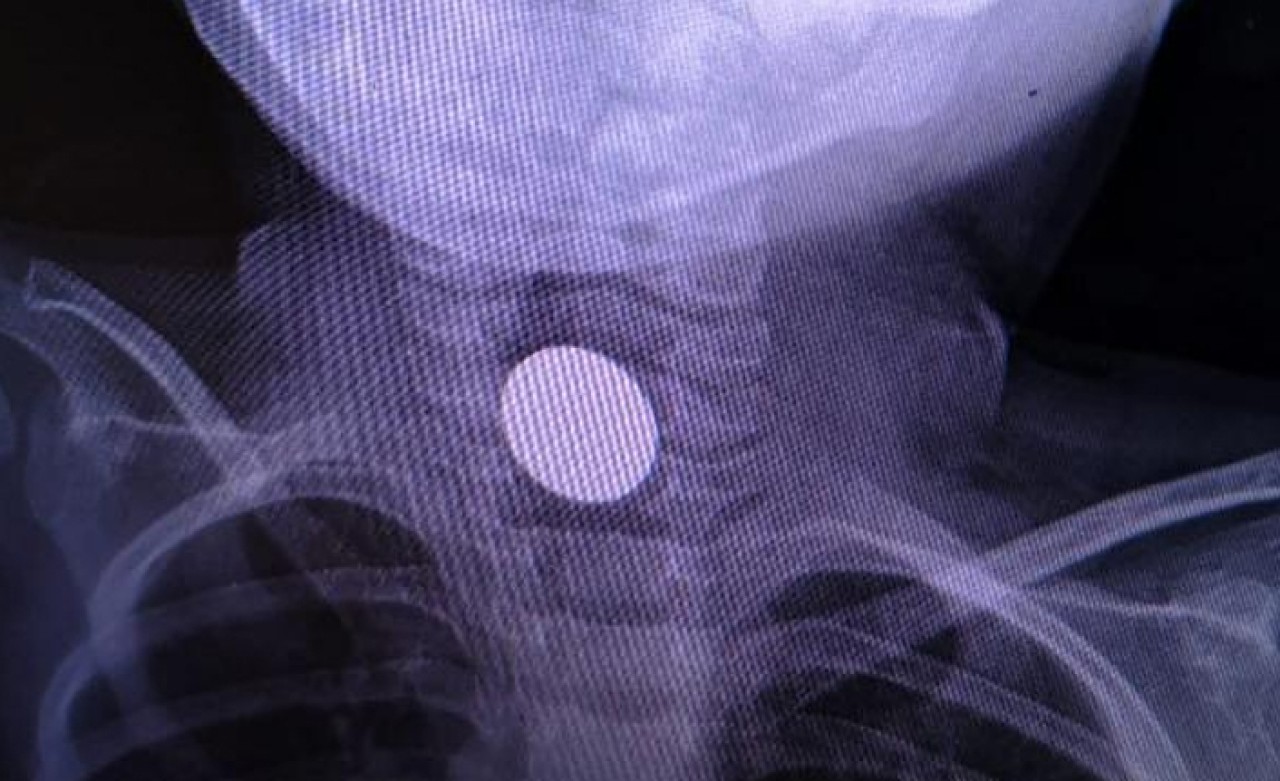

Madeni para, küçük çocuğun boğazına takıldı. Çocuk, ailesi tarafından İnegöl Devlet Hastanesi'ne götürüldü.

Burada yapılan ilk müdahalenin ardından küçük çocuk Bursa Şehir Hastanesi'ne sevk edildi. Madeni para, burada yapılan operasyon ile çıkartılırken, Yunus Emre Kaya'nın sağlık durumunun iyi olduğu öğrenildi.